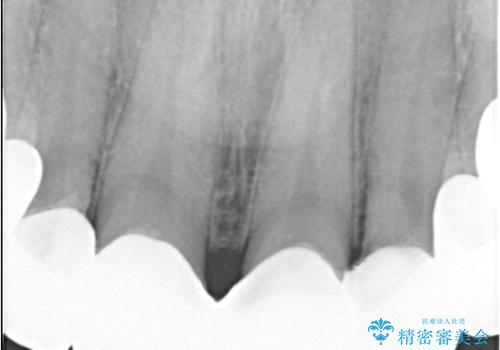

- 治療計画

治療では、まず古いクラウンを慎重に取り外し、歯肉の状態を整えました。その後、精密な型取りから患者様一人ひとりに合わせたオーダーメイドのオールセラミッククラウンを作製。金属を一切使用しないため、歯肉の変色を防ぎ、天然歯のような透明感と美しさを再現します。新しいクラウンは、歯肉のラインに合わせてぴったりと適合するよう調整し、見た目の違和感を解消。長年の悩みが解決し、自然で美しい口元と笑顔を取り戻していただけました。